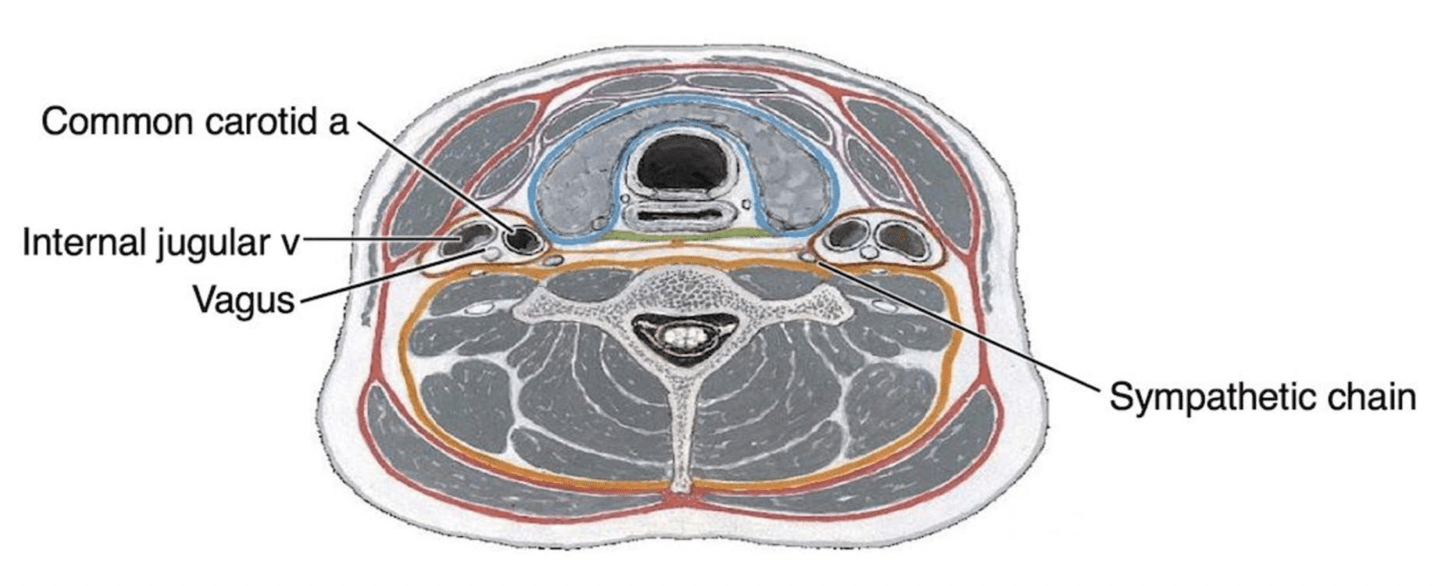

Horner’s syndrome may occur as a complication of carotid endarterectomy, during which sympathetic fibers associated with the common carotid artery can be damaged. This results in ptosis, miosis, and anhidrosis due to loss of sympathetic innervation to the face and eye. The descending sympathetic pathway that supplies these postganglionic fibers originates in which region of the brain?

Answer: Hypothalamus

The descending autonomic tract originates in the posterior hypothalamus and projects to preganglionic sympathetic neurons (T1–T2), and the sympathetic chain conveying these fibers lies outside the carotid sheath, where damage produces Horner’s syndrome with ptosis, miosis, and anhidrosis.